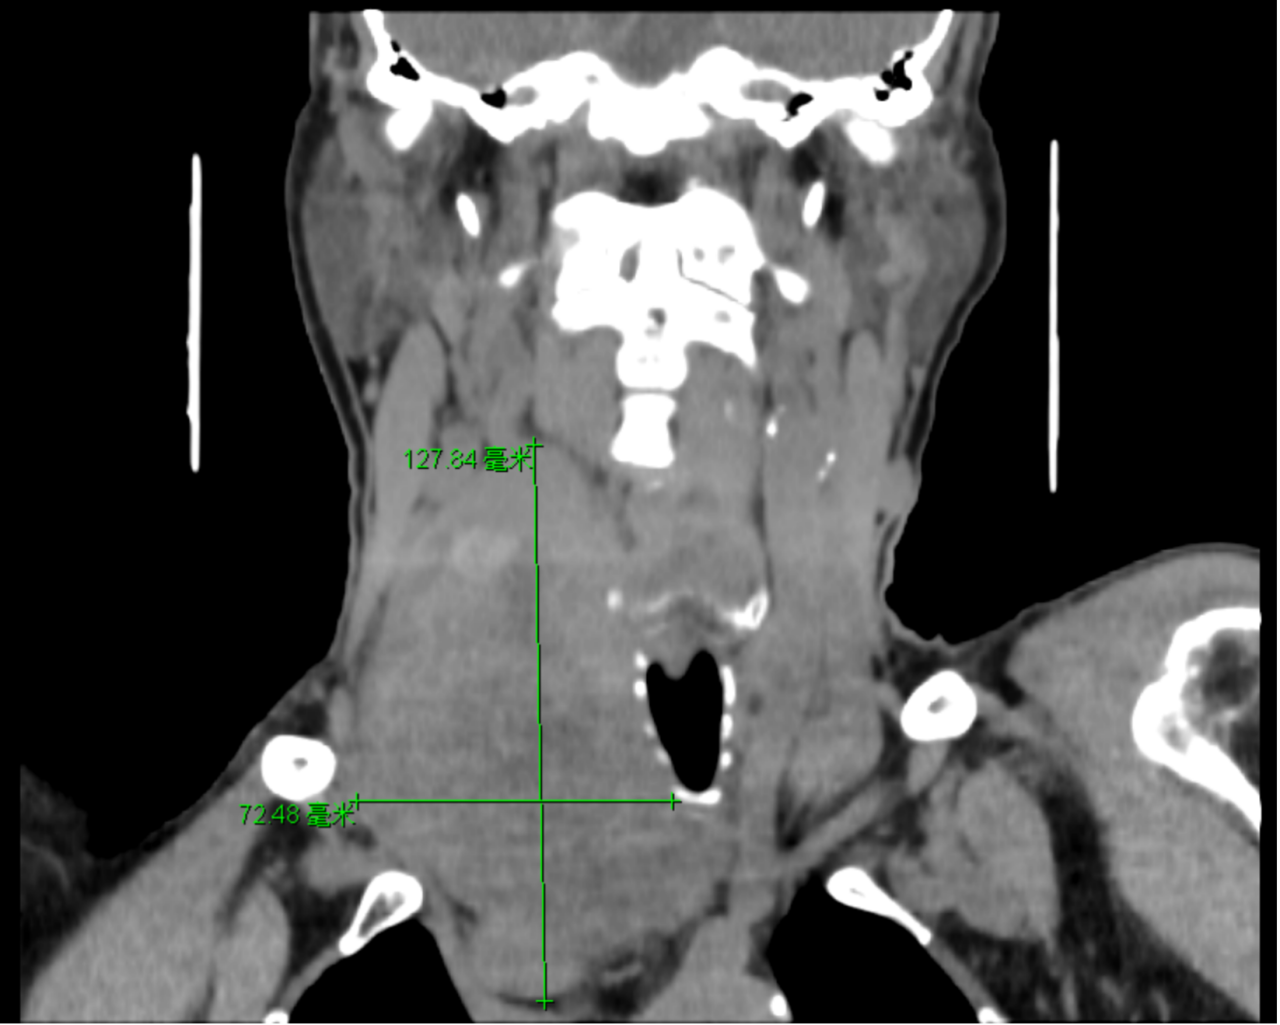

▲巨大胸骨后甲状腺肿

我院甲状腺(疝)外科肖雪明主任医师接诊后,发现吴伯伯患的是巨大胸骨后甲状腺肿,有12cm大!巨大肿块与周围组织黏连紧密,气管压迫严重并明显出现移位,再加上肿物已经向胸腔生长,延伸至胸骨后下4cm,紧靠主动脉弓,危害极大。

▲肿物大小达到12cm左右